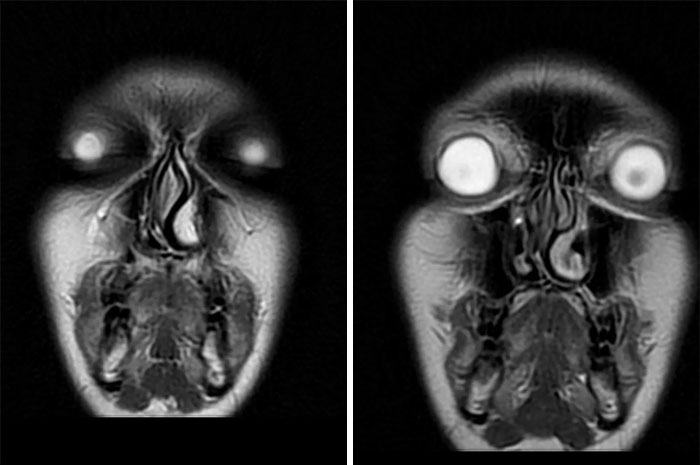

#39 My Mri Pictures Are Straight Up Nightmare Fuel

Image source: PatternConnect4039